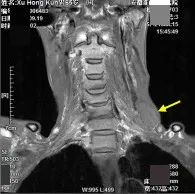

患者系左舌根部癌、左下颈部淋巴结转移,行维持治疗后复查。

冠状位T1WI图像

舌根部原发肿块

左颈部转移淋巴结

冠状位T2WI图像: